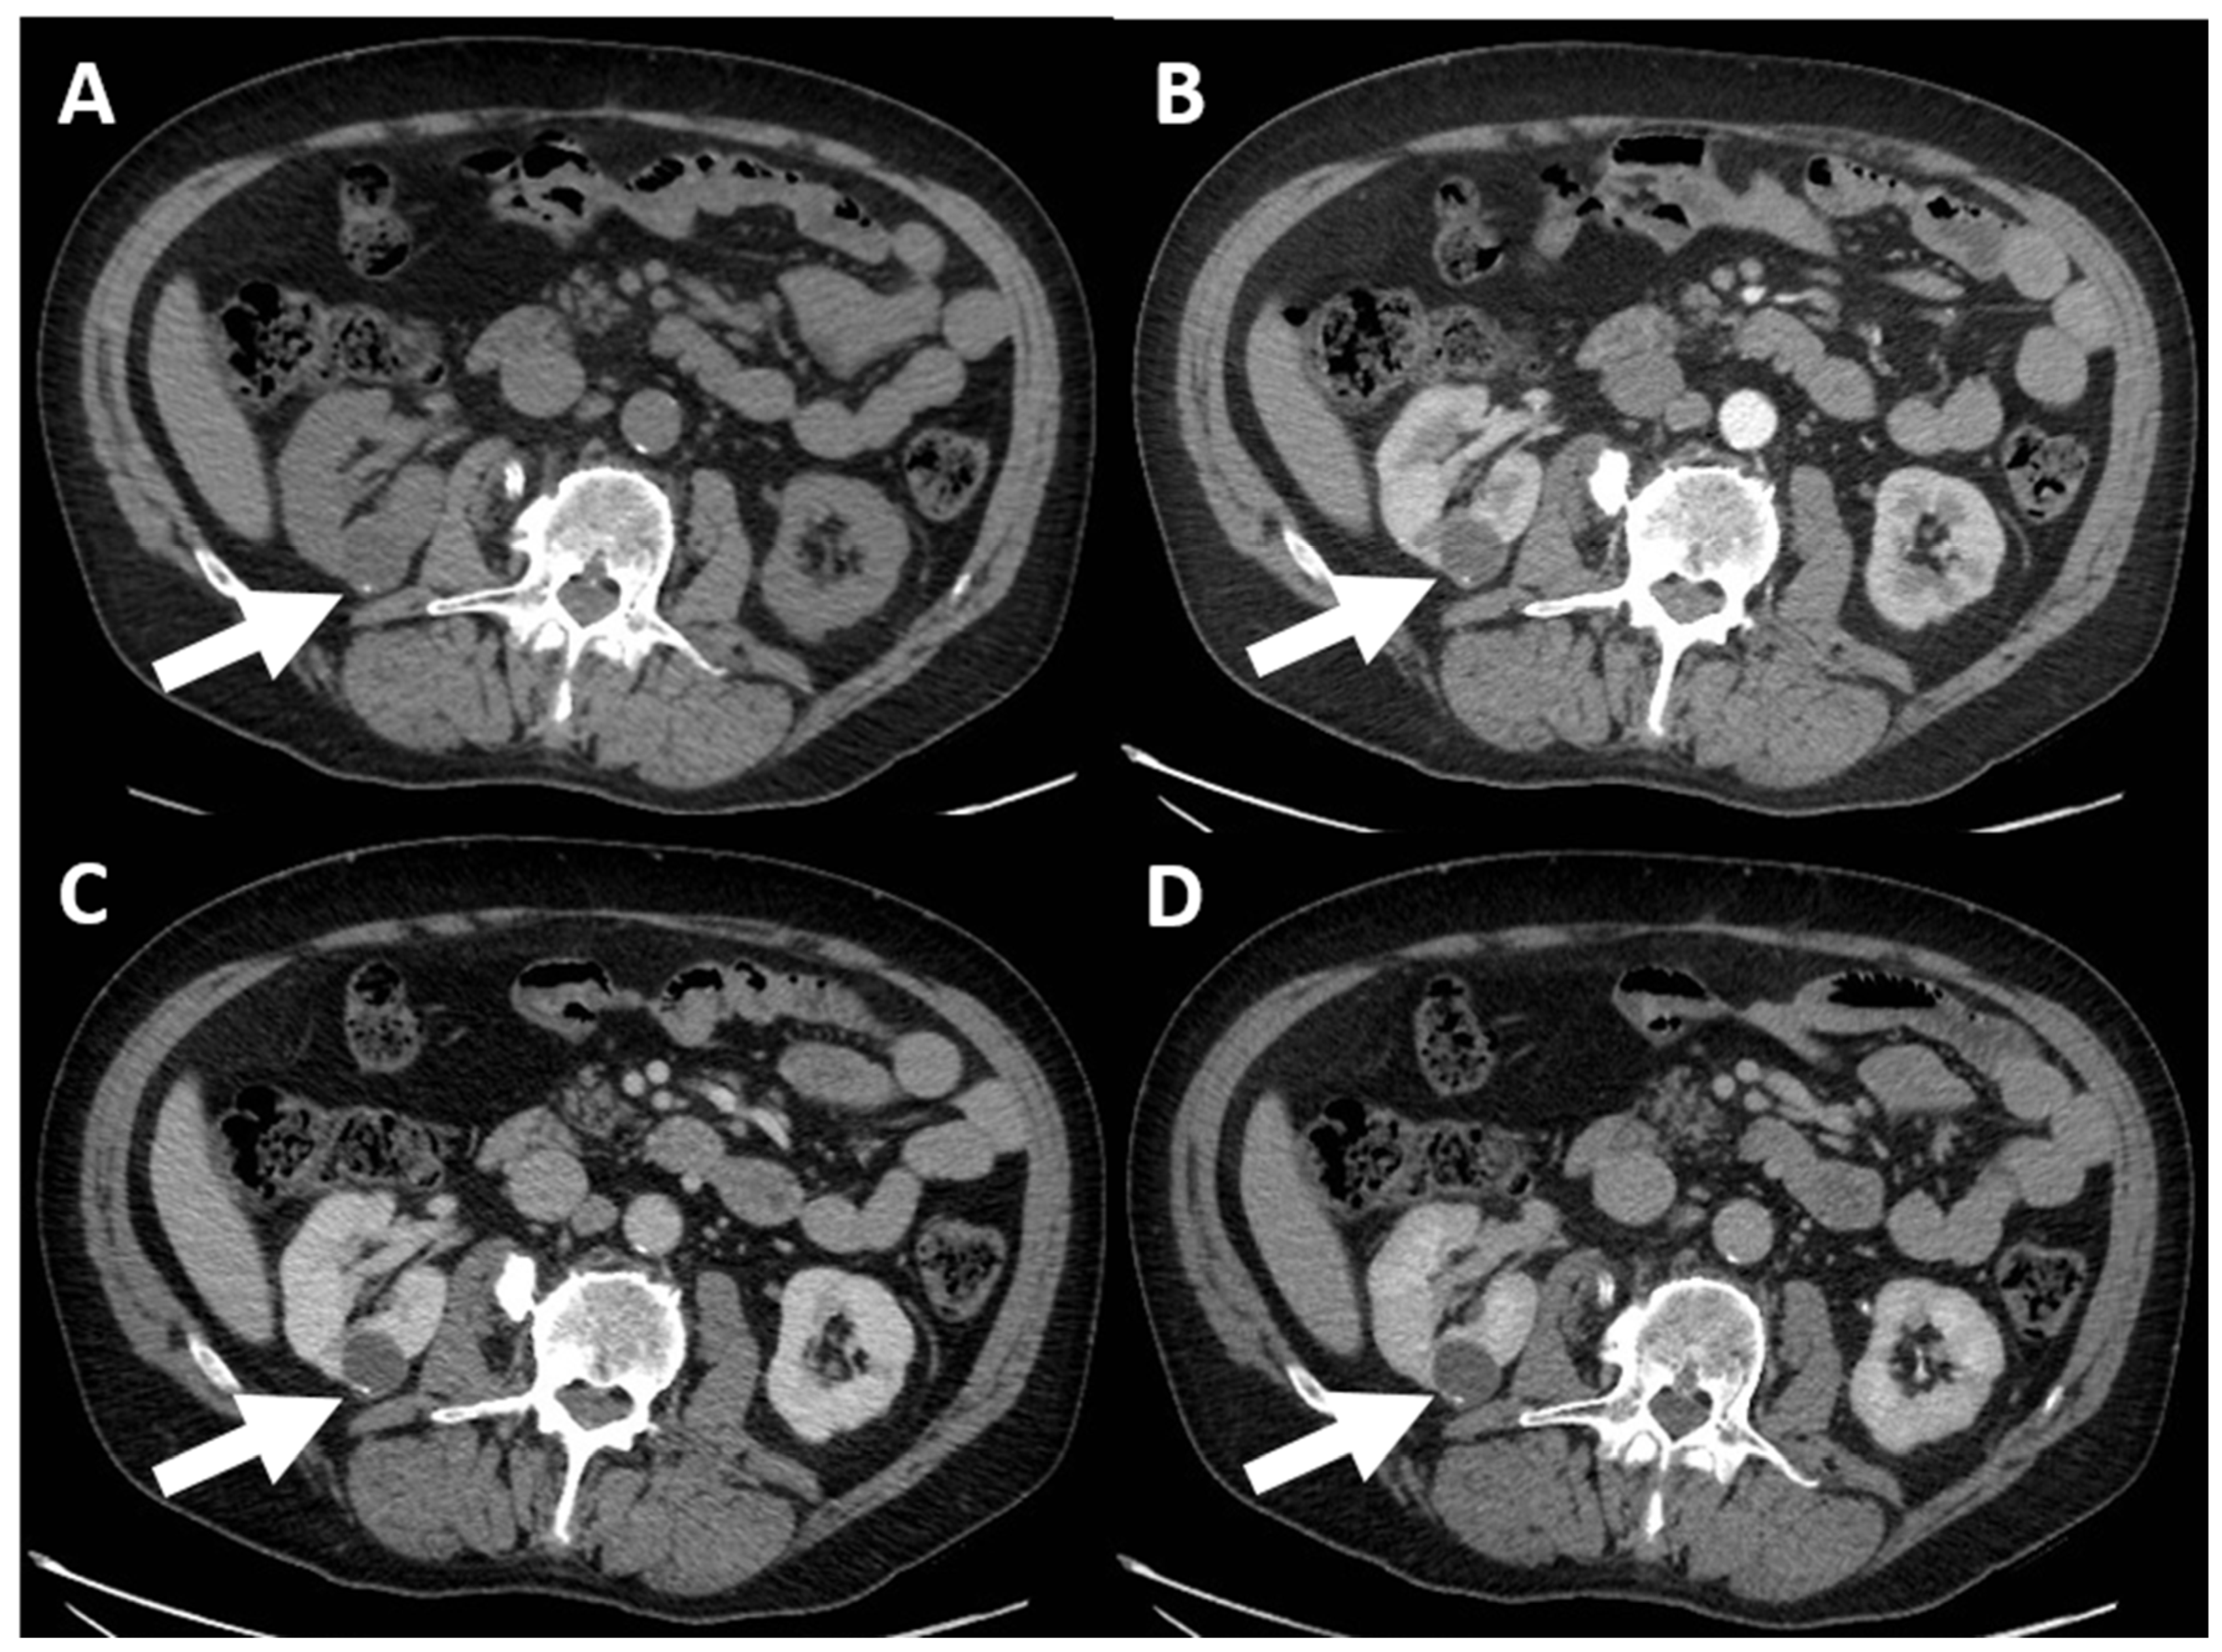

4. Computed Tomography Assessment

4.1. Lesion Density

4.3. Enhancement